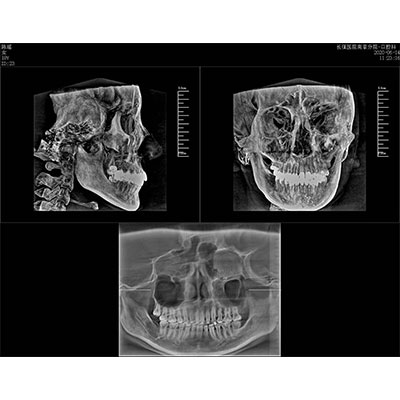

高清口腔三維CT/全景影像 PLX3000A

該款牙科CBCT產(chǎn)品采用動態(tài)平板探測器,獲得三維圖像的同時還具有數(shù)字化全景功能,廣泛應用于口腔頜面外科、正畸科、正頜外科、種植科、牙體科、顳下頜關節(jié)科等術前術后。

專有三維重建算法,可提供任意位置高清斷層影像。

通過三維容積影像,提取高清口腔全景影像。

可同時觀察軸向面、冠狀面和矢狀面圖像,方便臨床診斷。